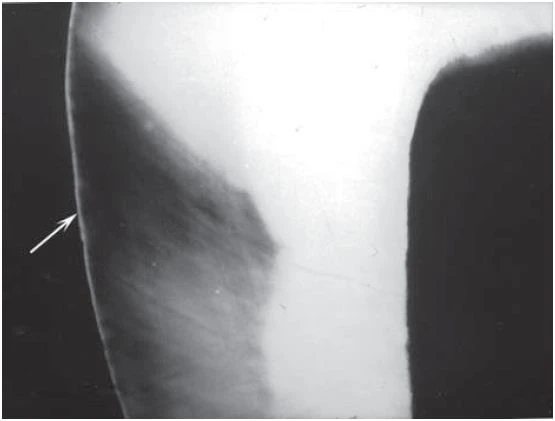

Phim bitewing (Hình 1) cho thấy không có tổn thương sâu răng tiến triển và đường viền xương mặt bên bình thường. Chỉ có một mối hàn amalgam nhỏ ở mặt nhai răng 46.

Hình 1: Phim cánh cắn ban đầu.